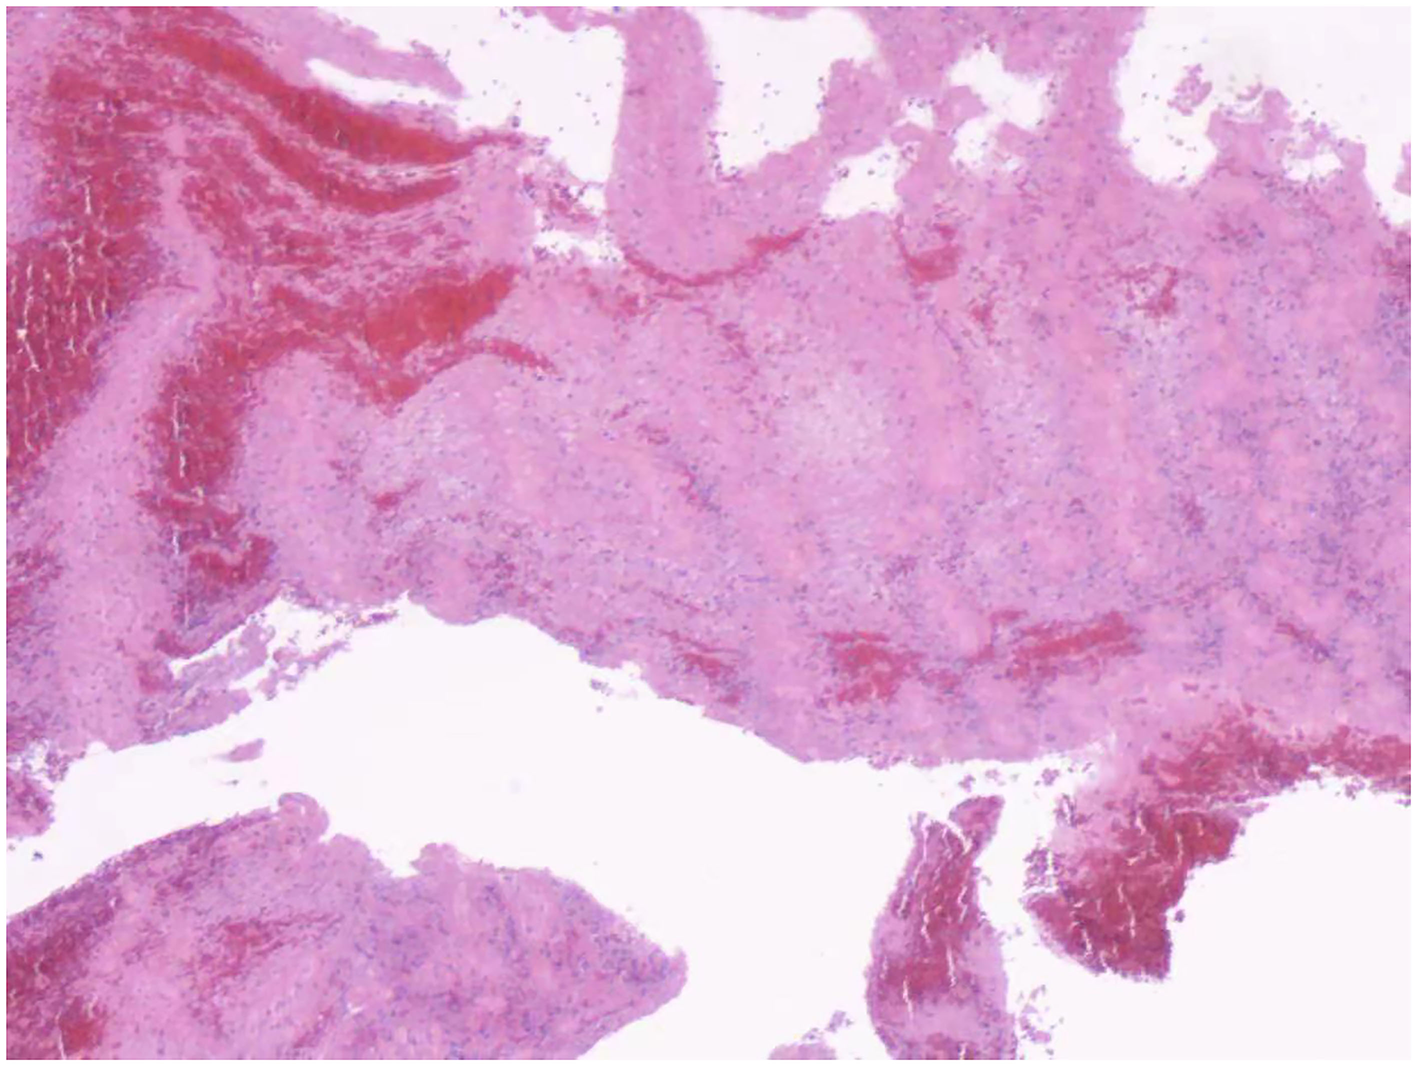

Figure 4

Hematoxylin and eosin stain presented a fresh thrombus that was rich in red blood cells and platelets.